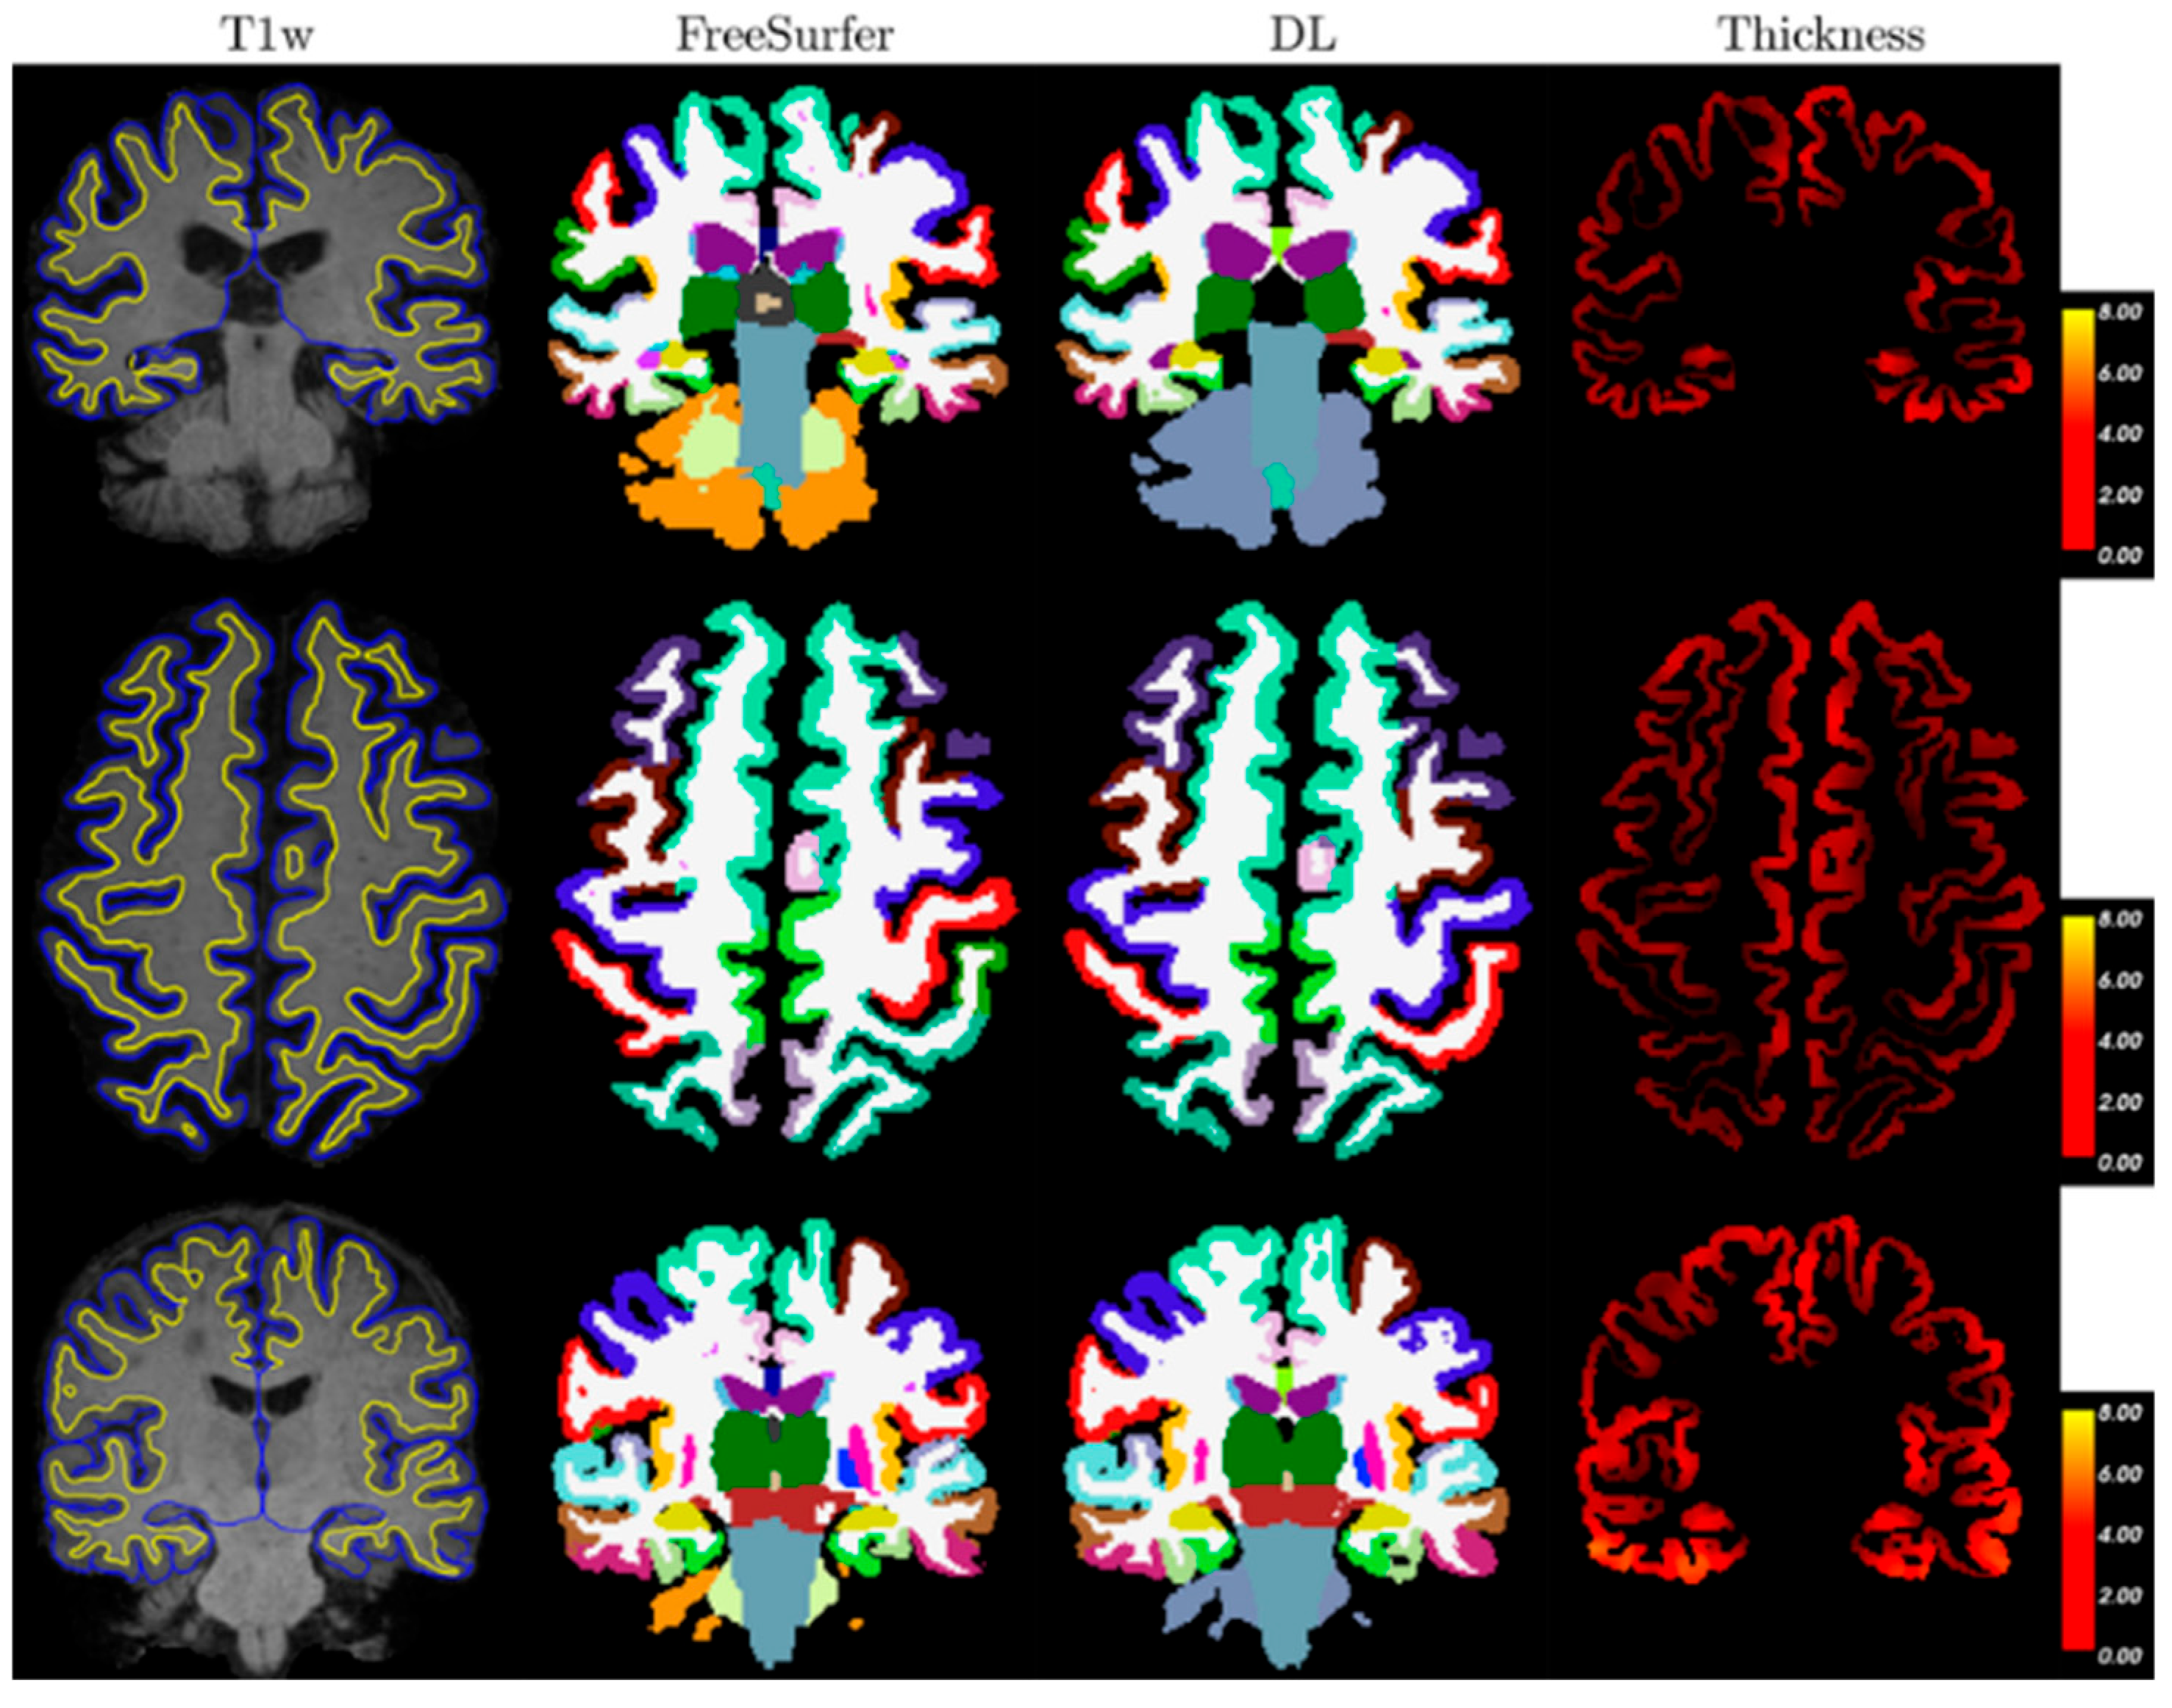

OASIS-3 aggregates ~15 years of imaging/clinical data from the Knight ADRC with ~1098 participants in the dataset release, including cognitively normal aging through symptomatic AD. It offers >2100 MRI sessions and ~1400–1500 PET sessions (amyloid and FDG) plus processed derivatives; many participants have multi-year longitudinal follow-up, enabling cross-sectional and progression analyses under open access [29,30]. Figure 7 shows three samples (one per row) from the OASIS-3 dataset. Columns show T1-weighted MRI with pial (blue) and a GM/WM (yellow) surface from FreeSurfer overlayed, segmentations from FreeSurfer and deep learning (DL), and a thickness map from DL+DiReCT. Slices are in radiological view (i.e., right hemisphere is on the left side of the image).

Figure 7. Three samples (one per row) from the OASIS-3 dataset [31].